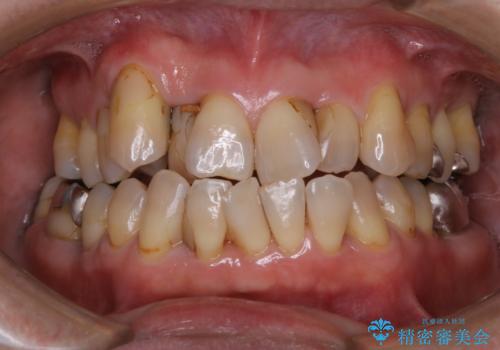

- これから、全体的な総合治療がスタートするため、着色や汚れをきれいにしてほしいとのことでした。PMTC60分コースを行いました。

PMTCとは「Professional Mechanical Tooth Cleaning」の略で、専用の機器を使った歯のクリーニングです。

PMTCは誰もが実施できるというわけではなく、歯科医師や歯科衛生士によるプロフェッショナルケアです。

また、治療が開始される前などにも、全体的にクリーニングを行いご自身本来の歯の色、状態を精密に確認することが大切です。